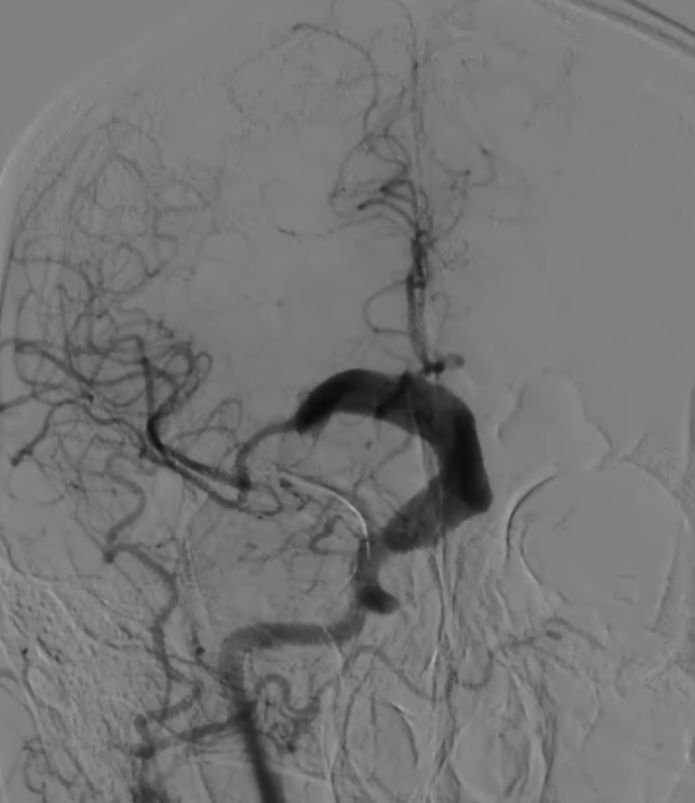

术前造影:

(1)右侧颈内动脉海绵窦段至颈内动脉末端巨大夹层动脉瘤伴血栓形成(图1)。

图1